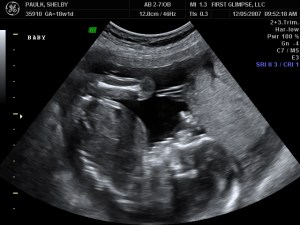

We had the ultrasound for baby number #2 on Tuesday, as we like to refer to HIM as (at least until we come up with a name, which could be a while given our track record). Yes, I said HIM…we are having a baby BOY!! We are so blessed to be have one of each. God is so good. Here are a few of the many ultrasound pictures that were taken. God has blessed us with one very healthy baby and we pray that this little guy is just as healthy. So far the docs. say everything looks great, we’ll have another ultrasound around 28 weeks because of where the placenta is located right now. It needs to move because it is blocking the cervix, but the ultrasound tech said that 9 of 1o times it will move…we pray that it does, because if it doesn’t I will have to have a C-Section.